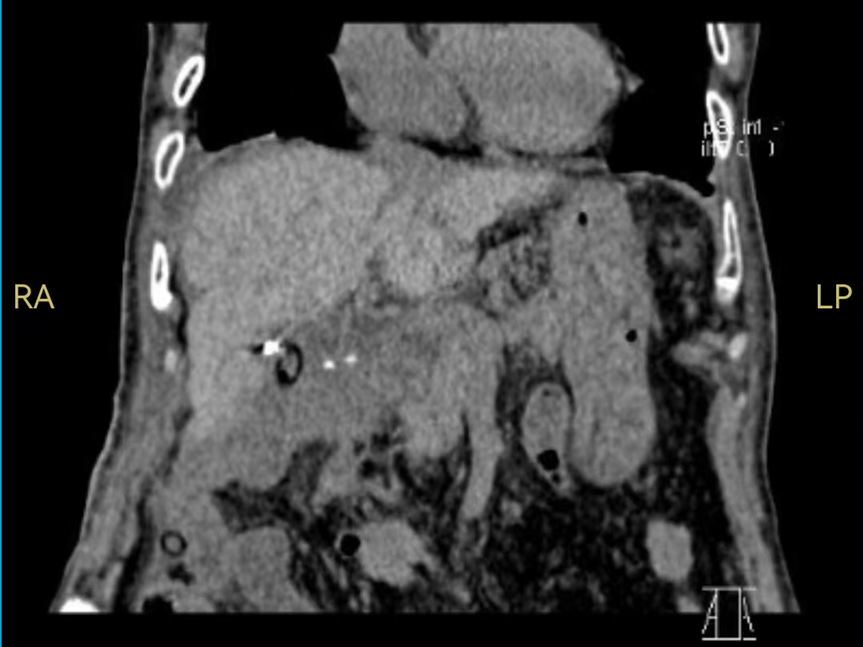

治疗后

尽管手术困难重重大,在肝胆胰医学中心王耀东教授、田毅峰教授带领下,陈忠副主任医师团队缜密评估,组织麻醉科、重症医学科、手术室等多学科讨论,最终制定完整的手术、麻醉及术后诊治方案。术中,团队在肝门区附近精雕细琢保护重要的入肝血管主干并完整切除肝癌病灶,吸尽周边积血并冲洗干净。术后老人顺利复苏,令人振奋的是,她在术后短时间内就恢复到生病前的状态。